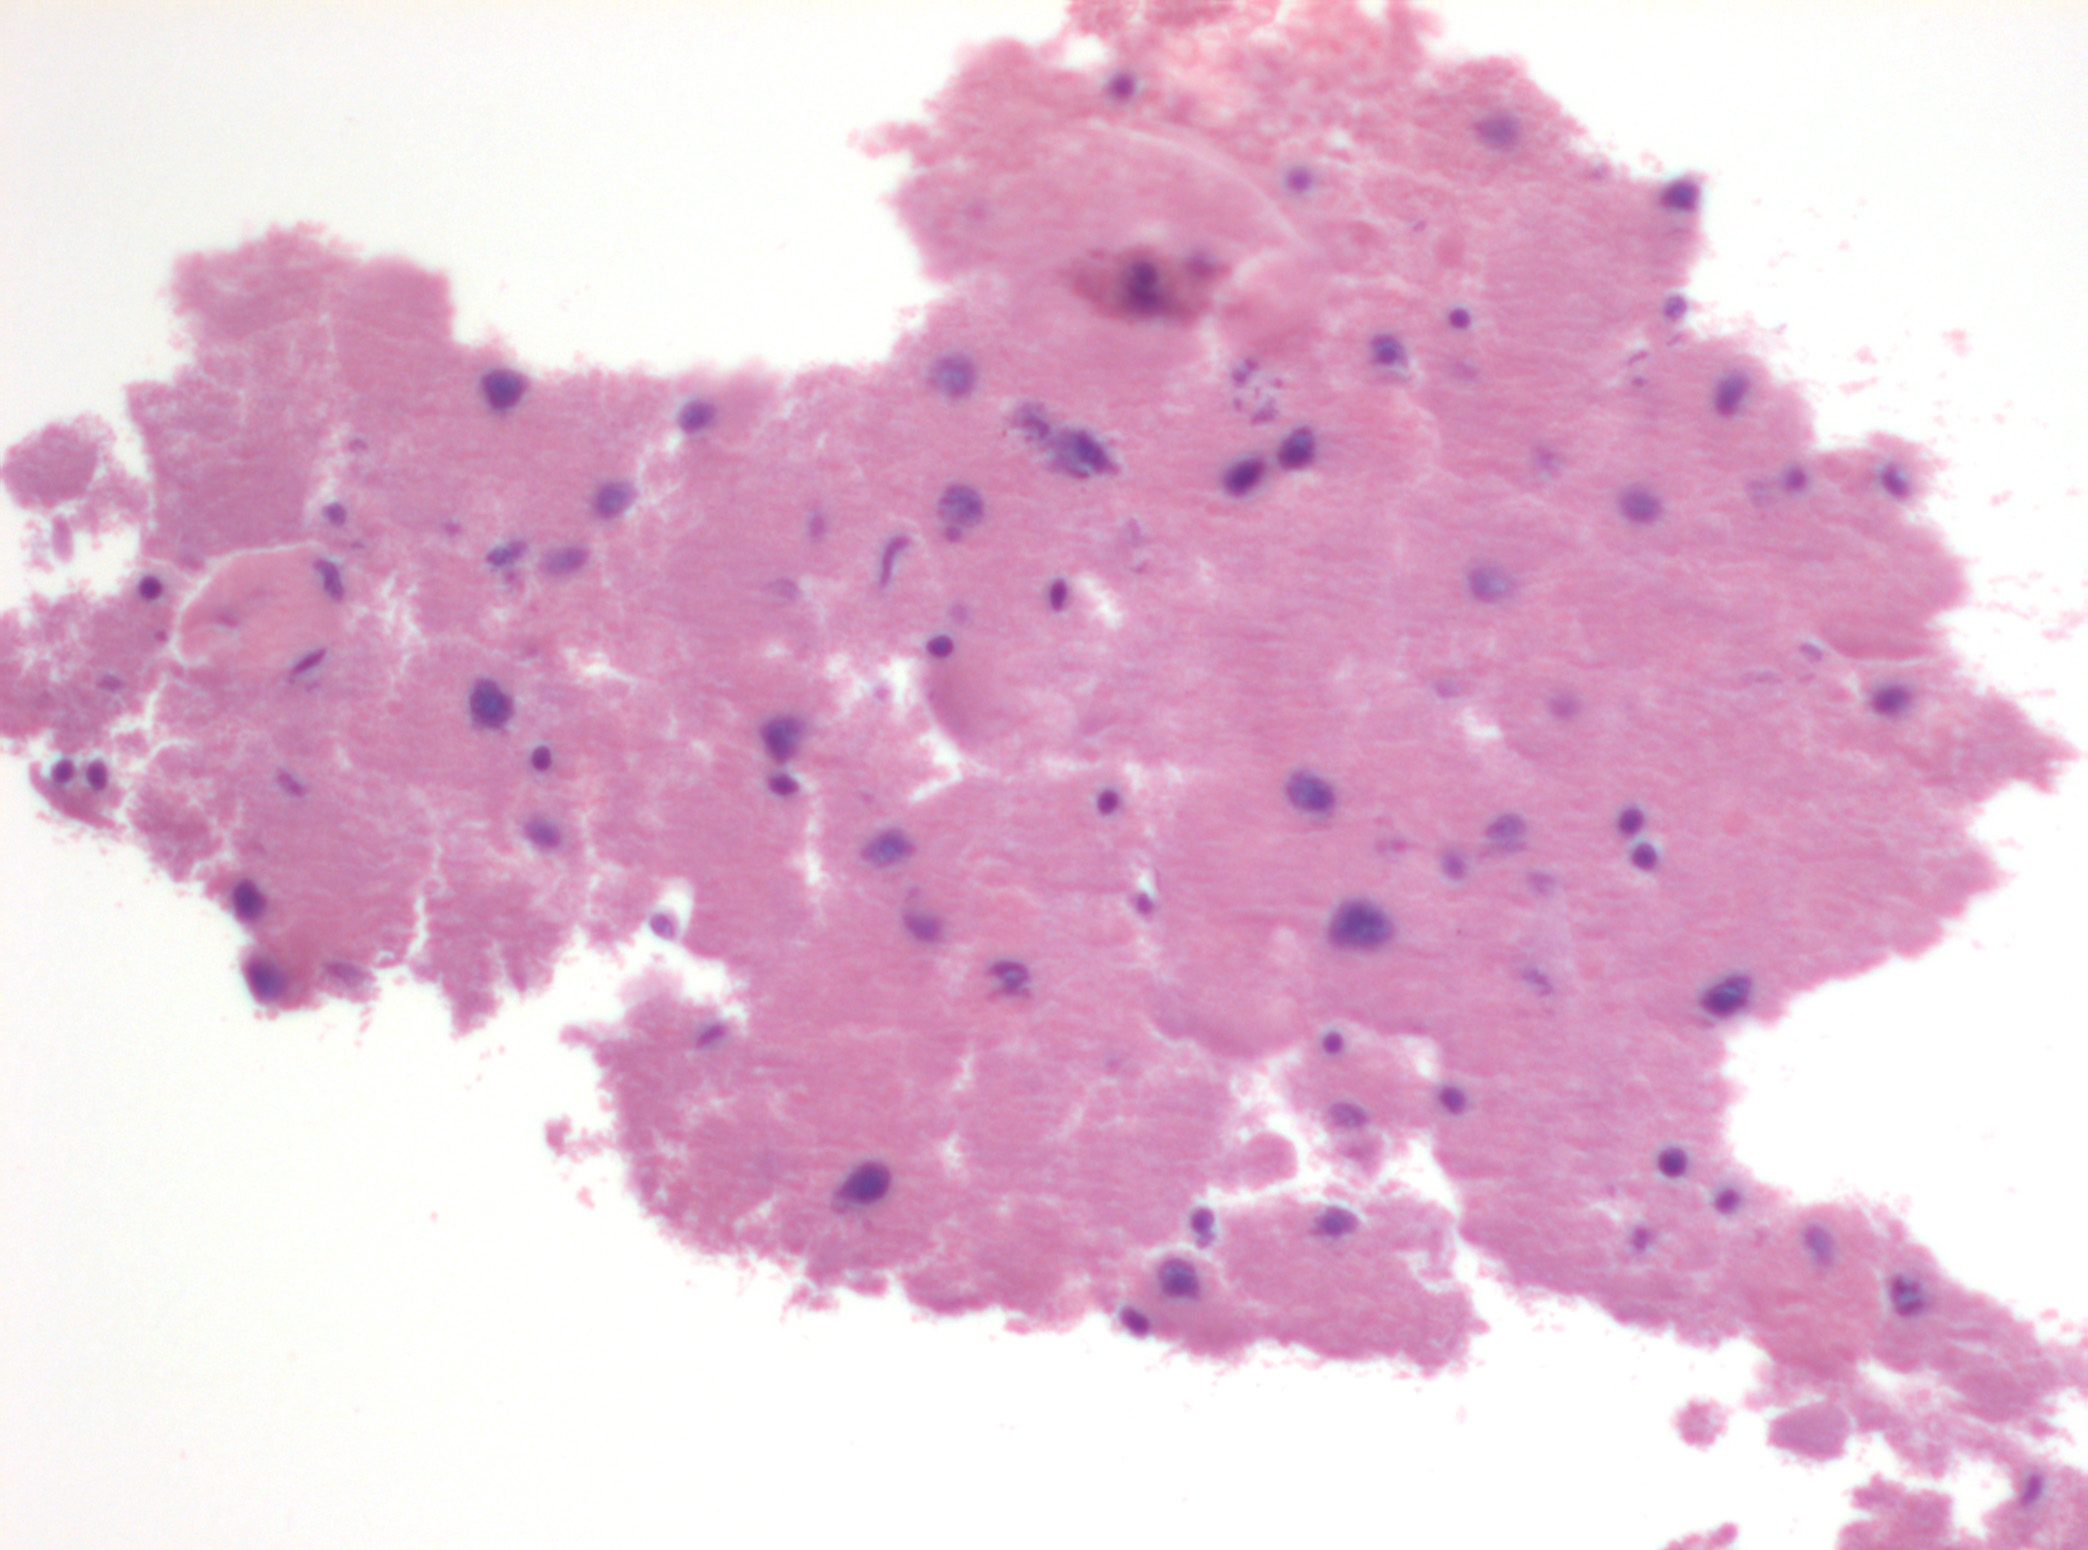

Dra. Mª Rosa Bella (patòleg) i Dr. Mario Prenafeta (radiòleg).

Hospital Universitari Parc Tauli Sabadell

Dona de 59 anys, fumadora de 15-20 cigarretes/dia fins fa 10 anys, sense altres hàbits tòxics destacables, amb antecedents patològics de Diabetes Mellitus tipus I que tracta amb insulina, Hipertensió arterial, i dislipèmia. Consulta per cuadre progressiu desde fa 5-6 mesos d'anosmia, cefalees hemicraneals esquerres, hipoestesia d'hemicara esquerra, epistaxis esquerres que es fan diàries, visió borrosa amb diplòpia, i tumefacció cervical esquerra. A l'exploració física s'observa exoftalmos esquerre i adenopaties laterocervicals esquerres indurades, i a l'estudi ORL s'observa lesió polipoidea eritematosa a fossa nasal provinent de meat superior esquerre. Es realitzen diverses proves de Diagnòstic per la imatge, i es realitzen simultàniament punció aspirativa i biòpsia de la lesió a fossa nasal. S'adjunten imatges de la RNM cranial, i de punció aspirativa.